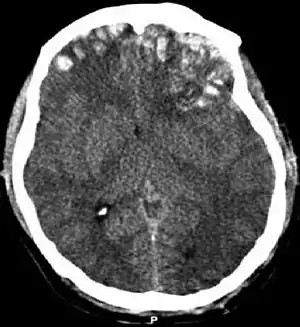

| CT scan showing cerebral contusions, hemorrhage within the hemispheres, subdural hematoma on the left, and skull fractures[1] | |

Cerebral contusion is a form of traumatic brain injury, a bruise of the brain tissue.[2] Like bruises in other tissues, cerebral contusion can be associated with multiple microhemorrhages, small blood vessel leaks into brain tissue. Contusion occurs in 20–30% of severe head injuries.[3] A cerebral laceration is a similar injury except that, according to their respective definitions, the pia-arachnoid membranes are torn over the site of injury in laceration and are not torn in contusion.[4][5] The injury can cause a decline in mental function in the long term and in the emergency setting may result in brain herniation, a life-threatening condition in which parts of the brain are squeezed past parts of the skull.[3] Thus treatment aims to prevent dangerous rises in intracranial pressure, the pressure within the skull.